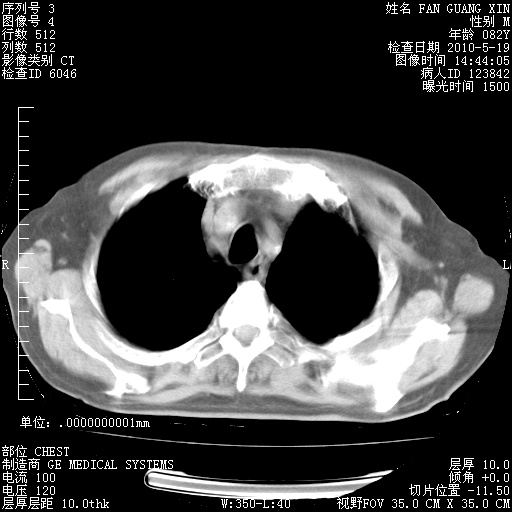

可改为口服强的松40-50mg/d治疗,若病情仍稳定,胸部阴影不再吸收可逐渐减量